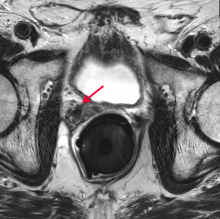

Boston Scientific has entered into a definitive agreement to acquire Augmenix Inc., a privately-held company which has developed and commercialized the SpaceOAR System to reduce common and debilitating side effects that men may experience after receiving prostate cancer radiotherapy. The transaction consists of an upfront cash payment of $500 million, and up to $100 million for reaching sales-based milestones.

According to the latest statistics from the American Cancer Society (ACS), almost 165,000 new cases of prostate cancer were expected in 2018, with over 29,000 men expected to die from the disease this year